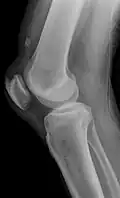

An x-ray demonstrating quadriceps tendon rupture. Note the abnormal angle of the patella and soft-tissue swelling marked by the arrow.